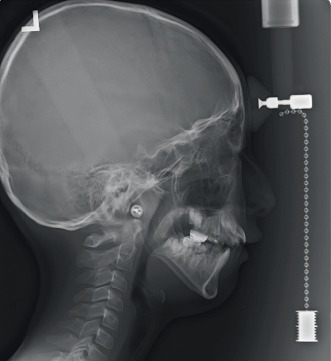

梅干腹综合征(PBS)是一种罕见的先天性疾病,以腹壁肌肉发育不全、泌尿系统异常和双侧隐睾为特征。本报告描述了一例罕见的PBS患者的畸形发育不全。病例介绍:一名患有PBS的10岁男孩,表现为言语和咀嚼困难。口腔及影像学检查显示异常发育不全的牙釉质缺损、下颌发育不全及后缩、上颌缩窄及前牙开咬。结论:虽然PBS的牙齿表现并不常见,但罕见的病例可能会出现异常的发育不全。

Introduction: Prune belly syndrome (PBS) is a rare congenital disease characterized by hypoplastic abdominal wall muscles, urological abnormalities, and bilateral cryptorchidism. This report describes a rare case of aberrant hypoplastic amelogenesis imperfecta in a patient with PBS. Case Presentation: A 10-year-old boy with PBS presented with difficulties in speech and mastication. Oral and radiological examinations revealed aberrant hypoplastic enamel defects, mandibular hypoplasia and retrusion, maxillary constriction, and anterior open bite. Conclusion: Although dental manifestations are not frequent in PBS, rare cases may present with aberrant hypoplastic amelogenesis imperfecta.